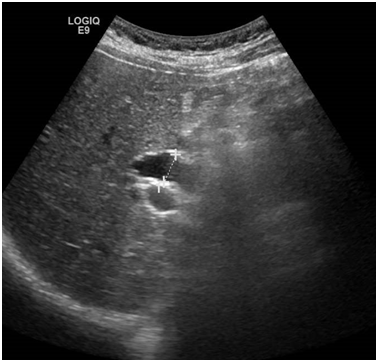

An abdominal and pelvic CT was performed and an unspecific thickening of the distal CBD wall was found (Figure 2). Endoscopic retrograde cholangiopancreatography (ERCP) showed an unspecific inflammation with friability of the Vater papilla and exuberant biliary tree dilation. Drainage of the biliary tree was obtained with a biliary plastic stent. Three weeks later, a second ERCP was performed, with stent removal and multiple ampulla biopsies were collected. Results of Pathology study showed in adenocarcinoma.

Figure 2 Celiac Axis stenosis in CT-scan.

In multidisciplinary assessment, our hepato-bilio-pancreatic radiologist highlighted a periampullar resectable tumor and a celiac axis significant stenosis. Diagnostic angiography was then performed, which confirmed the celiac axis stenosis and revascularization was attempted, but proven to be technically infeasible. Surgical resection was decided. Intraoperative hepatic artery flow was severely compromised with GDA occlusion, confirming the celiac axis stenosis. A supra-celiac-aorto-hepatic bypass graft (uni-graft K-DV 8mm) followed by a cephalic duodenopancreatectomy with a dunking pancreato-jejunostomy, end-to-side hepatico-jejunostomy and piloro-jejunostomy was performed (Figures 3 & 4).